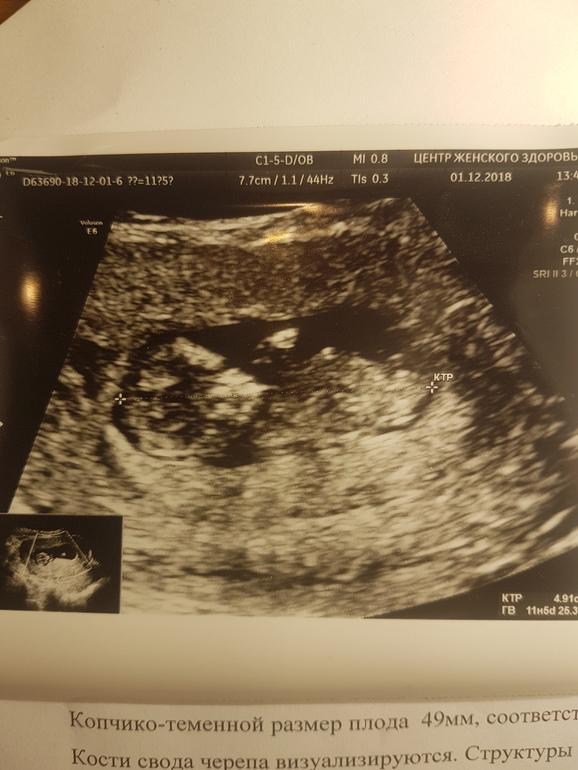

Волос от этого больше не стало. А так хотелось.В октябре мы увидели это:

Которое сейчас уже выглядит так:

Поэтому 2019 мы начнём так же, как и 2018. Будем делать ещё одну детскую.))